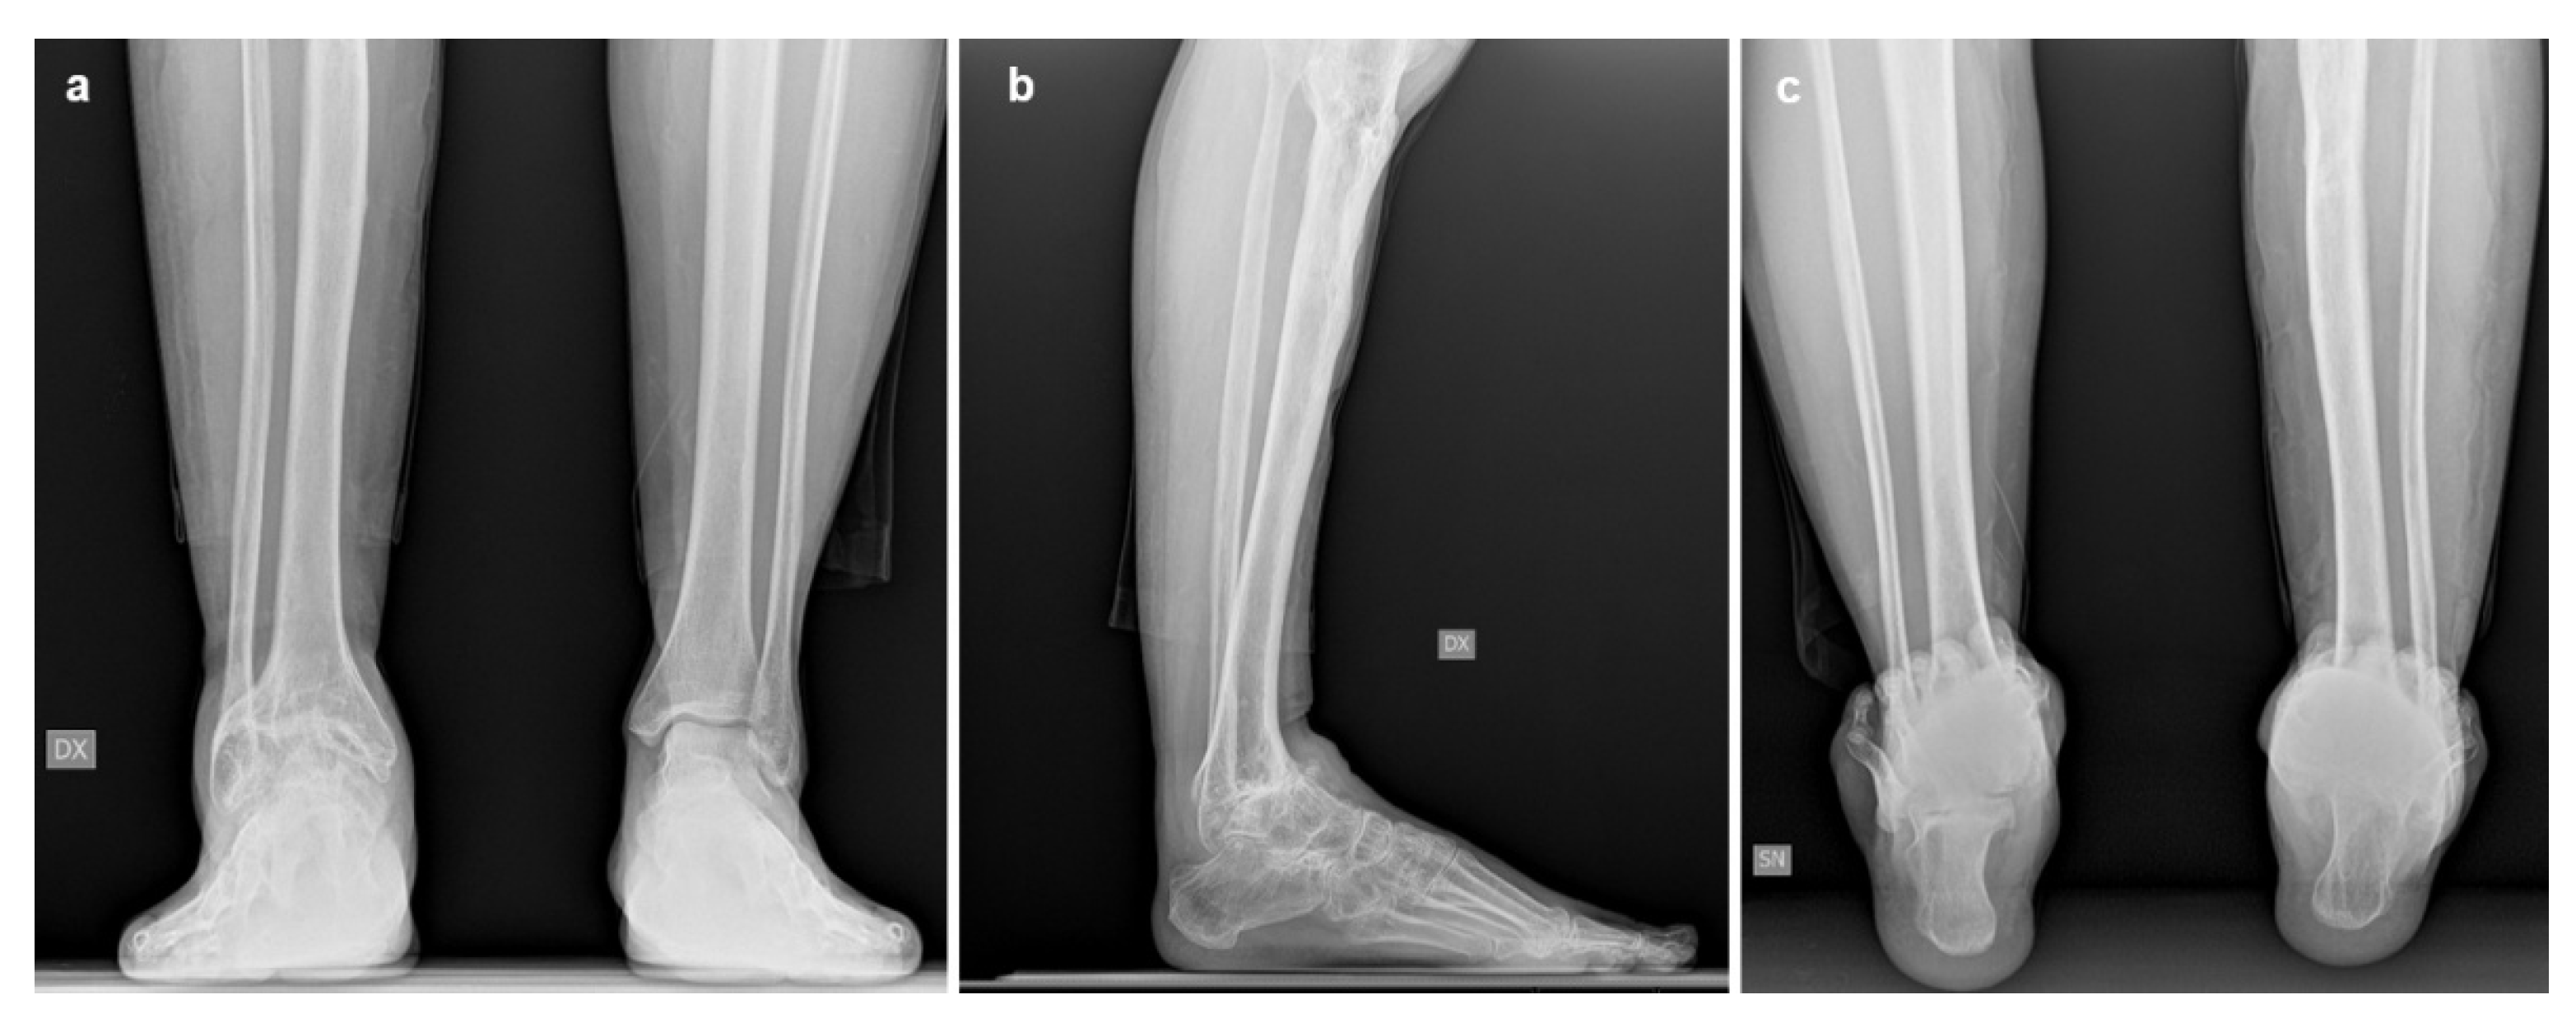

Imaging assessment included conventional bilateral foot and ankle weight-bearing radiographs in anteroposterior, lateral, and Saltzman views (Figure 1), as well as bilateral Weight-Bearing CT (WBCT) scans (Figure 2). Imaging demonstrated advanced right ankle osteoarthritis (Kellgren–Lawrence grade 4[8]) with severe distal tibial bone deformity.

Hindfoot and ankle alignment were fixed in varus and equinus, with an anterior shift of the talus relative to the tibia. Radiographic measurements, are summarized in Table 1.

At the 6-month follow-up, the patient had resumed her normal daily activities. Clinically, she demonstrated a smooth gait compatible with the ipsilateral knee fusion, with the hindfoot and ankle well aligned and stable. Ankle range of motion had improved to 40° of plantarflexion and 10° of dorsiflexion. Imaging confirmed a well-fixed and osseointegrated prosthesis with excellent ankle alignment (Figure 3). Post-operative radiographic measurements are summarized in Table 1. At the 36-month follow-up, imaging showed a stable implant with normal alignment. Clinically, the patient remained asymptomatic and pain-free (VAS 1), with maintained function and gait stability. The patient gave informed consent for the publication of her clinical details and images.

Figure 2. Preoperative weight-bearing computed tomography (WBCT) scans of Case one: (a) Coronal and (b) sagittal WBCT views demonstrating advanced tibiotalar osteoarthritis, distal tibial bone irregularities, and anterior talar shift.

Figure 3. Postoperative weight-bearing computed tomography (WBCT) scans of Case one: (a) coronal and (b) sagittal views at 3-year follow up, showing correct implant positioning, stable fixation, and no radiographic signs of loosening.